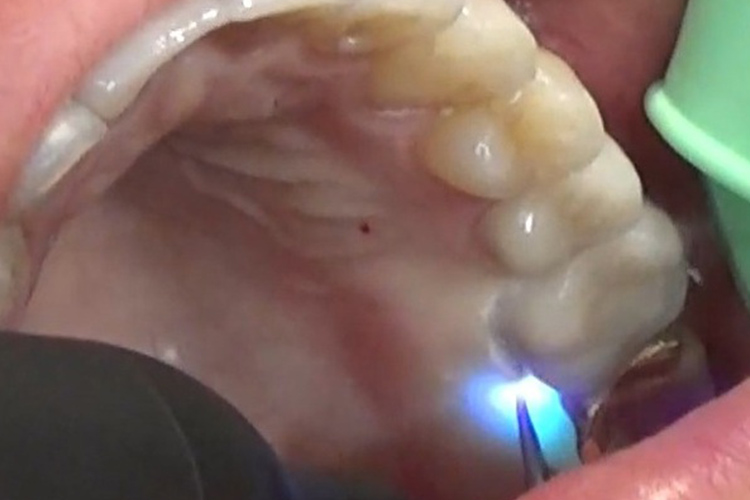

(施術風景)

深い歯周ポケットに青いレーザー光と過酸化水素水を照射し、患部を殺菌します。

(照射動画)